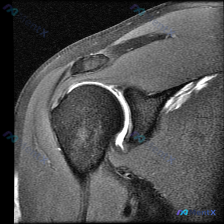

看到一份肩关节MRI-T2序列冠状位的病例资料,资料里提到患者怀疑有盂唇病变。先放影像的分析要点,大家一起讨论: 1. 关节积液:腋隐窝有明显类圆形高信号,提示关节腔内液体积聚 2. 肩袖肌腱:冈上肌腱在肱骨大结节附着处有异常高信号,连续性中断 3. 骨性结构:肱骨头与肩胛盂对位正常,无明显脱位或骨...

整理了一份肩部MRI-T2序列-冠状位的病例讨论材料。医生最初的关注点是盂唇病变,但影像上有几个点值得讨论: - 冈上肌腱在肱骨大结节附着处,纤维连续性中断,还有明确的高信号 - 肌腱远端有回缩,没完全覆盖肱骨头上方 - 肩峰下-三角肌下滑囊区域有条状高信号,像是积液 盂唇这里形态和信号倒没见明显异...

最近整理了一个肩关节MRI的病例讨论材料,用户的核心疑问是“盂唇病变”,但影像里还有几个点值得关注: 影像基本信息:肩关节MRI T2序列,冠状位切面 关键发现: 1. 冈上肌腱在肱骨大结节止点处有明显高信号,形态增厚,连续性欠佳 2. 肩峰下-三角肌下滑囊和关节腔内有大量高信号积液 3. 肩峰下间...